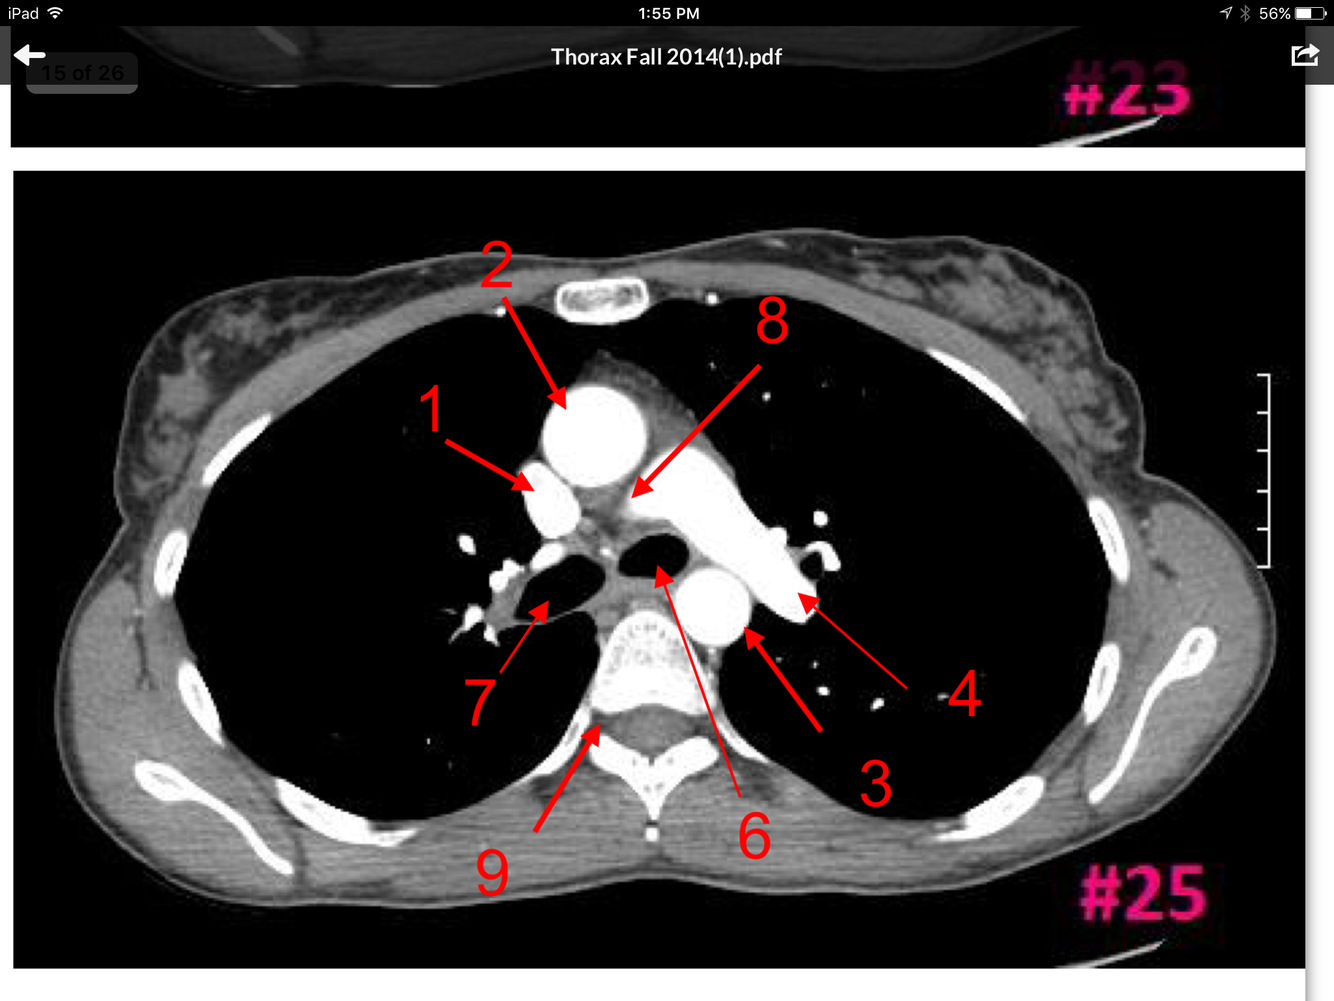

Superior vena cava

Ascending aorta

Descending aorta

Lt pulmonary artery

Lt main bronchus

Rt main bronchus

Rt pulmonary artery

Rt intervertebral foramen